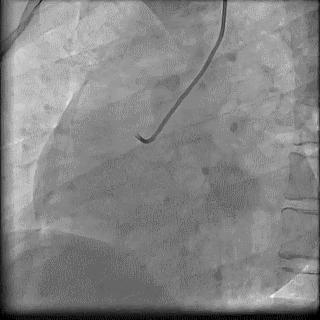

(4)LIMA桥血管造影

首选导管:JR4.0导管

其他导管:如果开口明显成角应选用专用的内乳动脉造影导管

➢ CASE 6

经股动脉途径TIG,非选择造影如果能清晰显影,可不做超选造影

➢ CASE 7

经左侧桡动脉途径JR4.0,非选择造影如果能清晰显影,可不做超选造影